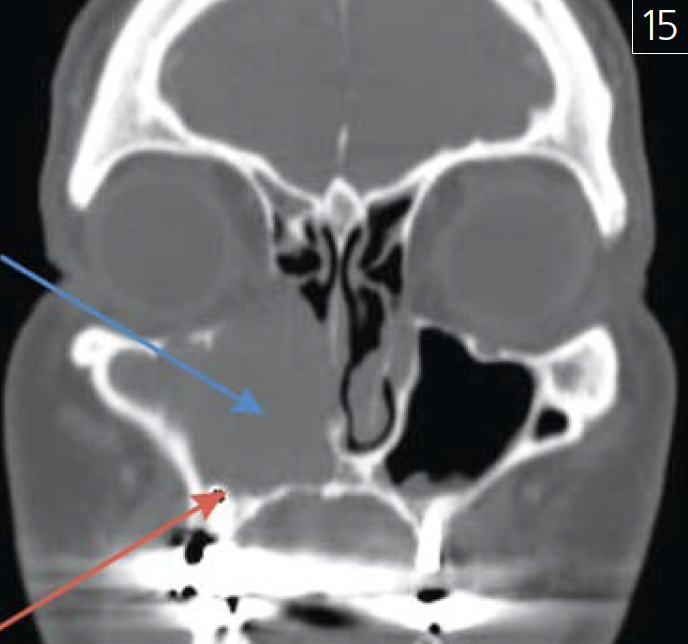

Особое место в практике врача-стоматолога, челюстно-лицевого хирурга и рентгенолога занимают ятрогении (рис. 13 а-в; 14 а, б; 15 а-в; 16; 17).

Рис. 13. Амелобластома нижней челюсти слева: а – фронтальный срез КЛКТ челюстей(патологический участок указан красной стрелкой); б – аксиальный срез КЛКТ нижней челюсти(“треугольник Кодмана”, рентгенологический признак опухоли, указан голубой стрелкой);в – гистологический препарат опухоли, окрашенный гематоксилином и эозином, увеличение 200:1

Рис. 15. Установка дентального имплантата(указан красной стрелкой) в карциному верхнейчелюсти справа (указана синей стрелкой) –фронтальная проекция МСКТ черепа